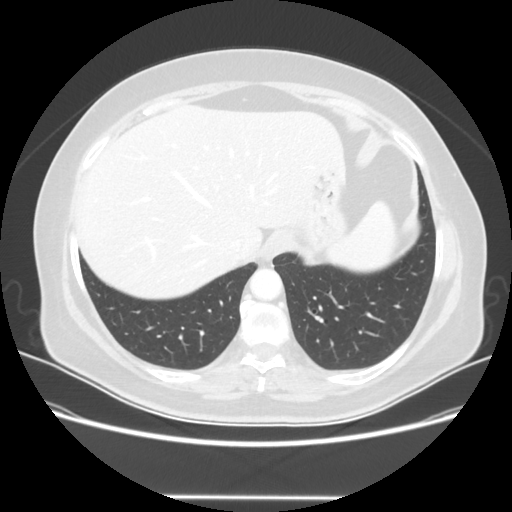

Original VENOUS CT scan

Full window (WL 1023.5, WW 4095 β†’ Low βˆ’1024, High +3071)

Actual HU range: [-1024.0, 884.0]

Lung window (WL -600, WW 1500 β†’ Low βˆ’1350, High +150)

Actual HU range: [-1350.0, 150.0]